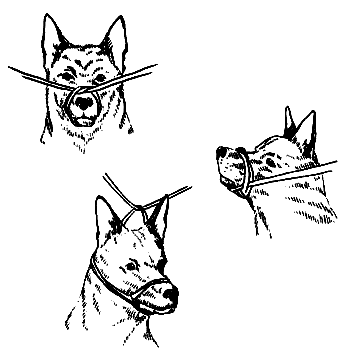

Если собака испытывает сильную боль (например, при переломах и травмах), она становится агрессивной. С таким животным следует вести себя крайне осторожно, ни в коем случае не приближая лицо к морде животного. Чтобы избежать укусов, необходимо завязать морду животного.

Для этого берут кусок ткани, марлю или веревку и завязывают ее в виде петли вокруг морды собаки таким образом, чтобы животное не могло открыть пасть. Затем концы повязки еще раз обматывают вокруг морды собаки и снова завязывают. Третий узел делают на затылке животного. Завязывая собаке морду, нужно следить, чтобы повязка не была слишком тугой и не препятствовала дыханию.

Как правильно завязать морду собаке